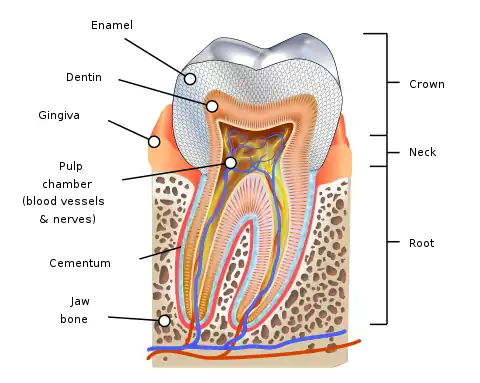

A root canal is the naturally occurring anatomic space within the root of a tooth. It consists of the pulp chamber (within the coronal part of the tooth), the main canal(s), and more intricate anatomical branches that may connect the root canals to each other or to the surface of the root.

Structure

At the center of every tooth is a hollow area that houses soft tissues, such as the nerve, blood vessels, and connective tissue. This hollow area contains a relatively wide space in the coronal portion of the tooth called the pulp chamber. These canals run through the center of the roots, similar to the way graphite runs through a pencil. The pulp receives nutrition through the blood vessels, and sensory nerves carry signals back to the brain. A tooth can be relieved from pain if there is irreversible damage to the pulp, via root canal treatment.

Root canal anatomy consists of the pulp chamber and root canals. Both contain the dental pulp. The smaller branches, referred to as accessory canals, are most frequently found near the root end (apex), but may be encountered anywhere along the root length. The total number of root canals per tooth depends on the number of the tooth roots ranging from one to four, five or more in some cases. Sometimes there are more than one root canal per root. Some teeth have a more variable internal anatomy than others.

The space inside the root canals is filled with a highly vascularized, loose connective tissue, called dental pulp. The dental pulp is the tissue of which the dentin portion of the tooth is composed. The dental pulp helps complete formation of the secondary teeth (adult teeth) one to two years after eruption into the mouth. The dental pulp also nourishes and hydrates the tooth structure, making the tooth more resilient, less brittle and less prone to fracture from chewing hard foods. Additionally, the dental pulp provides a hot and cold sensory function.